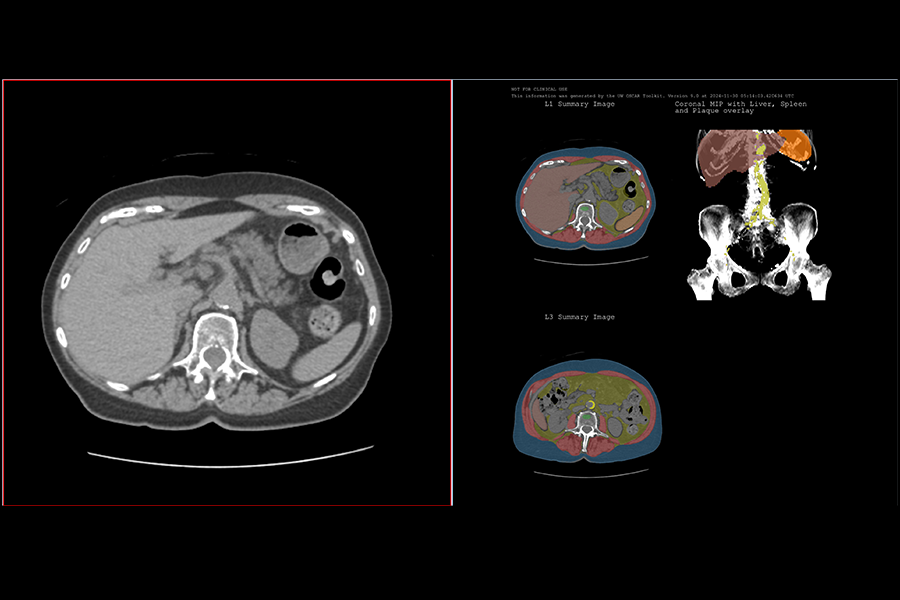

Dr. Pickhardt joined the Abdominal Imaging and Intervention Section at the University of Wisconsin School of Medicine and Public Health in 2003 as an Associate Professor (CHS) of Radiology and was Promoted to professor (CHS) in 2009, and Professor with Tenure in 2019. In 2024, he was named the John R. Cameron Professor of Radiology & Medical Physics. He continues to serve as the Chief of Gastrointestinal Imaging. CT colonography and colorectal cancer screening continue to be among Dr. Pickhardt’s clinical and research interests, along with machine learning/artificial intelligence, oncologic imaging, and opportunistic CT screening. His work in abdominal imaging has resulted in over 500 scientific publications and book chapters, as well as multiple textbooks. Among other honors, he has received seven best paper awards at the Annual Meeting for the Society of Abdominal Radiology and was named the “Most Influential Radiology Researcher” by auntminnie.com in 2016 and again in 2023. In 2024, he received the Gold Medal from the Society of Abdominal Radiology. He has also served as a PI on multiple NIH R01 grants.

AuntMinnie awarded Perry Pickhardt, MD this year’s Minnie in the category of “Most Influential Radiology Researcher.” The award recognizes his work on automated AI body composition tools for opportunistic computed tomography (CT) screening.